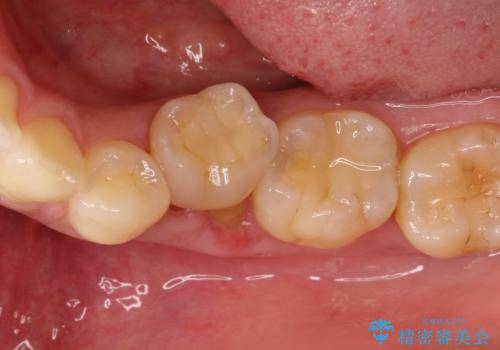

奥歯が痛い。乳歯を抜歯し、ブリッジによる咬合回復。

- 晩期残存した乳歯が痛くなったことを主訴に来院されました。

歯周病が進行していたため、抜歯を行い咬合回復を行いました。

インプラントは希望されなかったため、ブリッジにて治療を行っております。